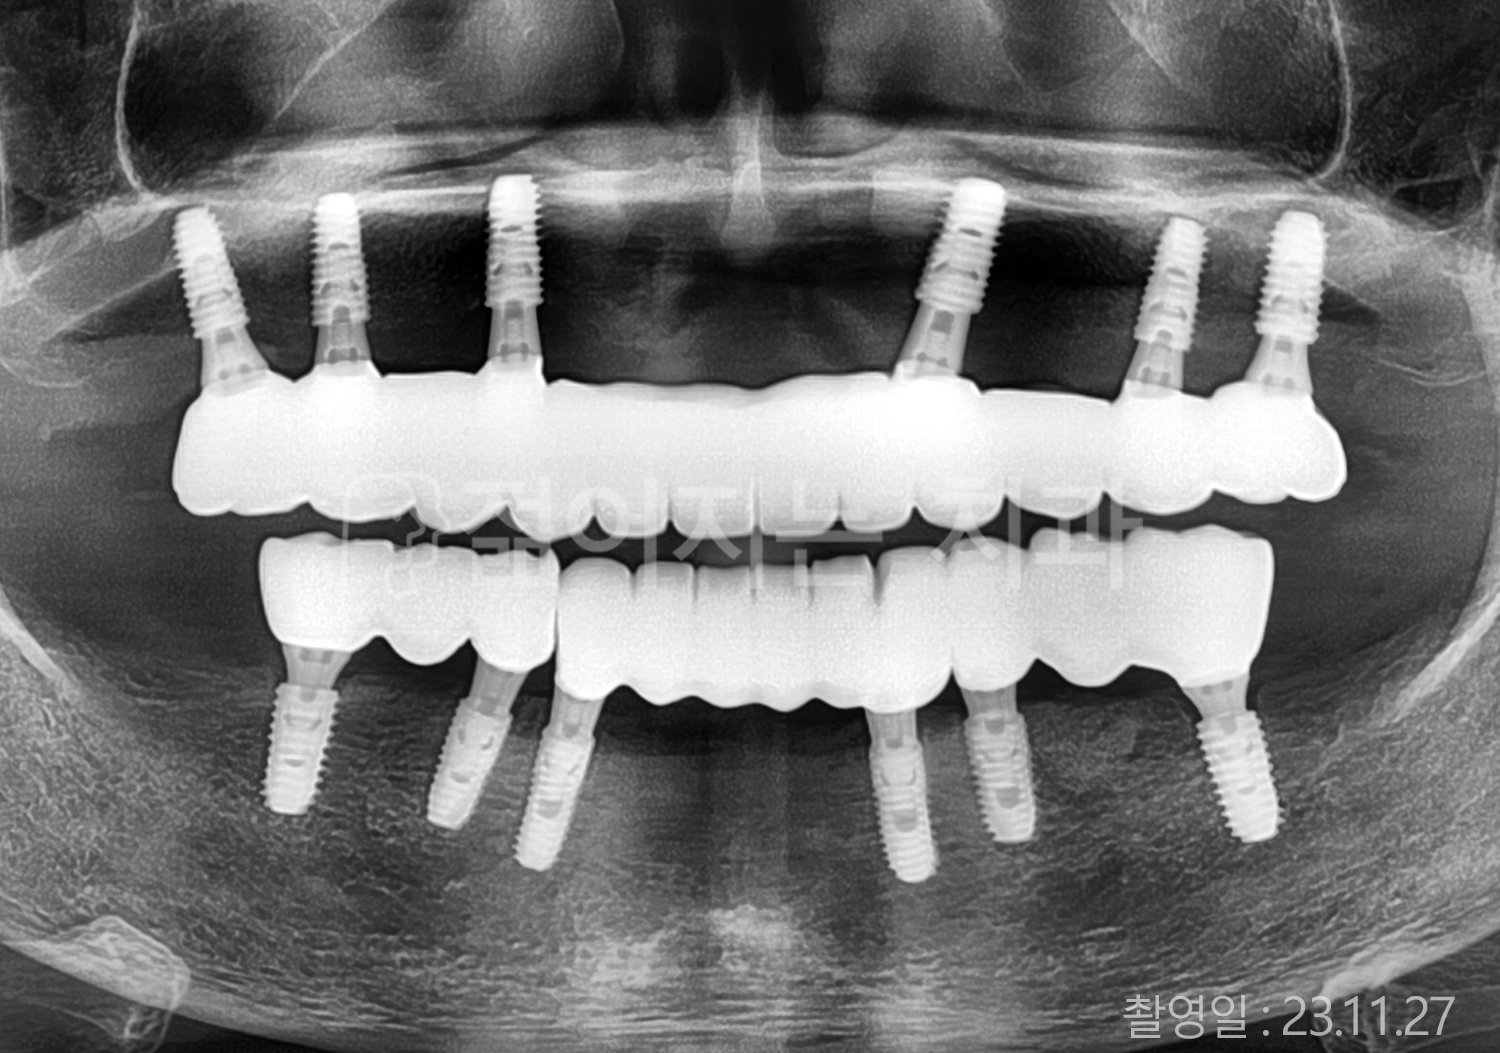

치료부위

식립개수

특이사항

• 50대 전체치아 10개 이상 임플란트